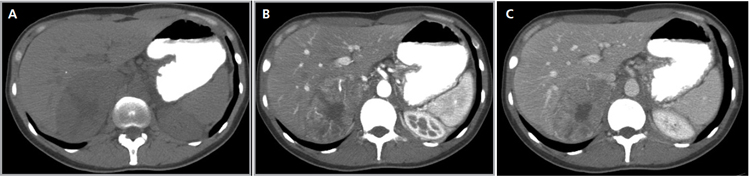

Los valores más utilizados son un 40% de lavado relativo de en fase tardía realizada a los 15 minutos y un lavado absoluto de 60%. De este modo cualquier lesión que muestre un lavado relativo mayor al 40% o absoluto mayor al 60% es consistente con un adenoma, con una sensibilidad y especificidad cercana al 100% (Figura 14 a, b y c). Dado la rapidez con que se obtiene un TAC de abdomen en la actualidad, algunos trabajos han recomendado utilizar cortes tardíos realizados a los 10 minutos, con el fin de optimizar el tiempo de examen, y utilizar un valor relativo de corte más conservador del 50%9.

A

B

C Figura 14. Tomografía computada de un adenoma suprarrenal izquierdo típico. Se ha colocado un circulo que representa la región de interés en la lesión de la glándula suprarrenal izquierda, obteniendo una medición promedio (Avg) expresada en unidades Hounsfield (UH). En fase precontraste (a) su densidad es de 0 UH, (flecha), en fase protovenosa (b) alcanza una densidad de 59 UH (cabeza de flecha), y en fase tardía (c) su lavado es de aproximadamente un 50%, llegando a una densidad de 30 UH.